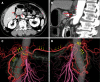

Background: During pancreaticoduodenectomy in patients with celiac axis (CA) stenosis due to compression by the median arcuate ligament (MAL), the MAL has to be divided to maintain hepatic blood flow in many cases. However, MAL division often fails, and success can only be determined intraoperatively. To overcome this problem, we performed endovascular CA stenting preoperatively, and thereafter safely performed pancreaticoduodenectomy. We present this case as a new preoperative treatment strategy that was successful.

Case summary: A 77-year-old man with a diagnosis of pancreatic head cancer presented to our department for surgery. Preoperative assessment revealed CA stenosis caused by MAL. We performed endovascular stenting in the CA preoperatively because we knew that going into the operation without a strategy could lead to ischemic complications. Double-antiplatelet therapy (DAPT) - which is needed when a stent is inserted - was then administered in parallel with neoadjuvant chemotherapy (NAC). This allowed us to administer DAPT for a sufficient period before the main pancreaticoduodenectomy procedure while obtaining therapeutic effects from NAC. Subtotal stomach-preserving pancreaticoduodenectomy was then performed. The operation did not require any unusual techniques and was performed safely. Postoperatively, the patient progressed well, without any ischemic complications. Histopathologically, curative resection was confirmed, and the patient had no recurrence or complications due to ischemia up to six months postoperatively.